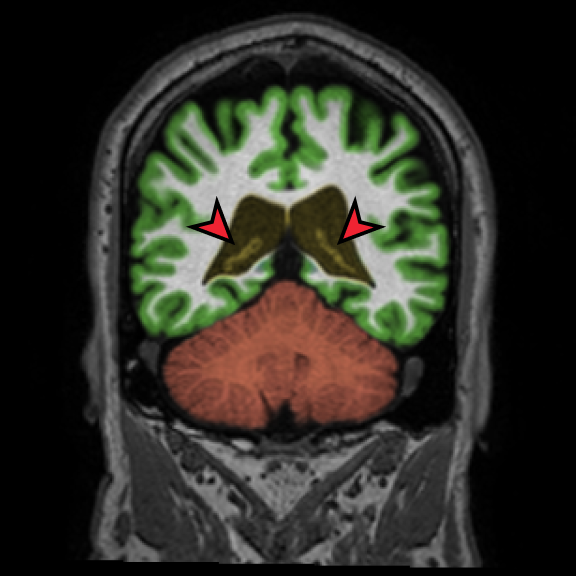

Longitudinal Tracking

Alzheimer's Disease Case Study 1

Retrospective brain volumetric analysis in a female patient diagnosed with Alzheimer’s disease at age 77 showed progressive brain atrophy over a 5-year period. The scans demonstrate both hippocampal volume loss and a clear left–right asymmetry.

PATIENT

Female patient diagnosed with Alzheimer's Disease at Age 77

Analysis period

5 years

regions of interest

Hippocampi

Inferior lateral ventricles

Age 72

Age 76

Age 77

Whole brain